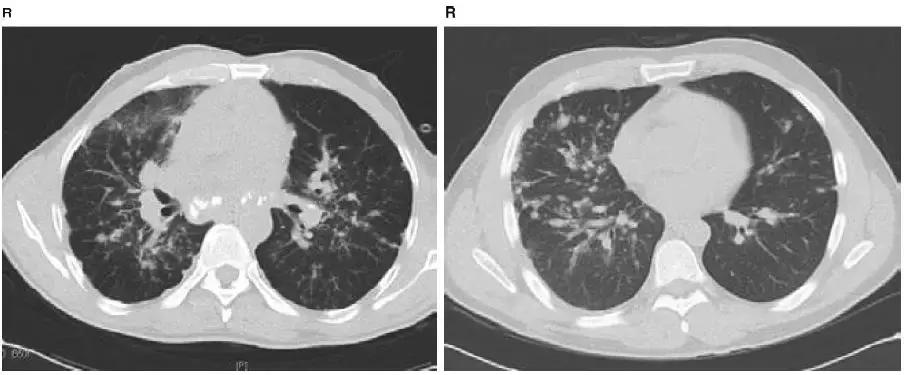

图4-24 Ⅱ期结节病CT:显示淋巴结钙化,肺实质浸润

图4-25 Ⅱ期结节病CT:显示沿支气管血管束分布的结节状阴影